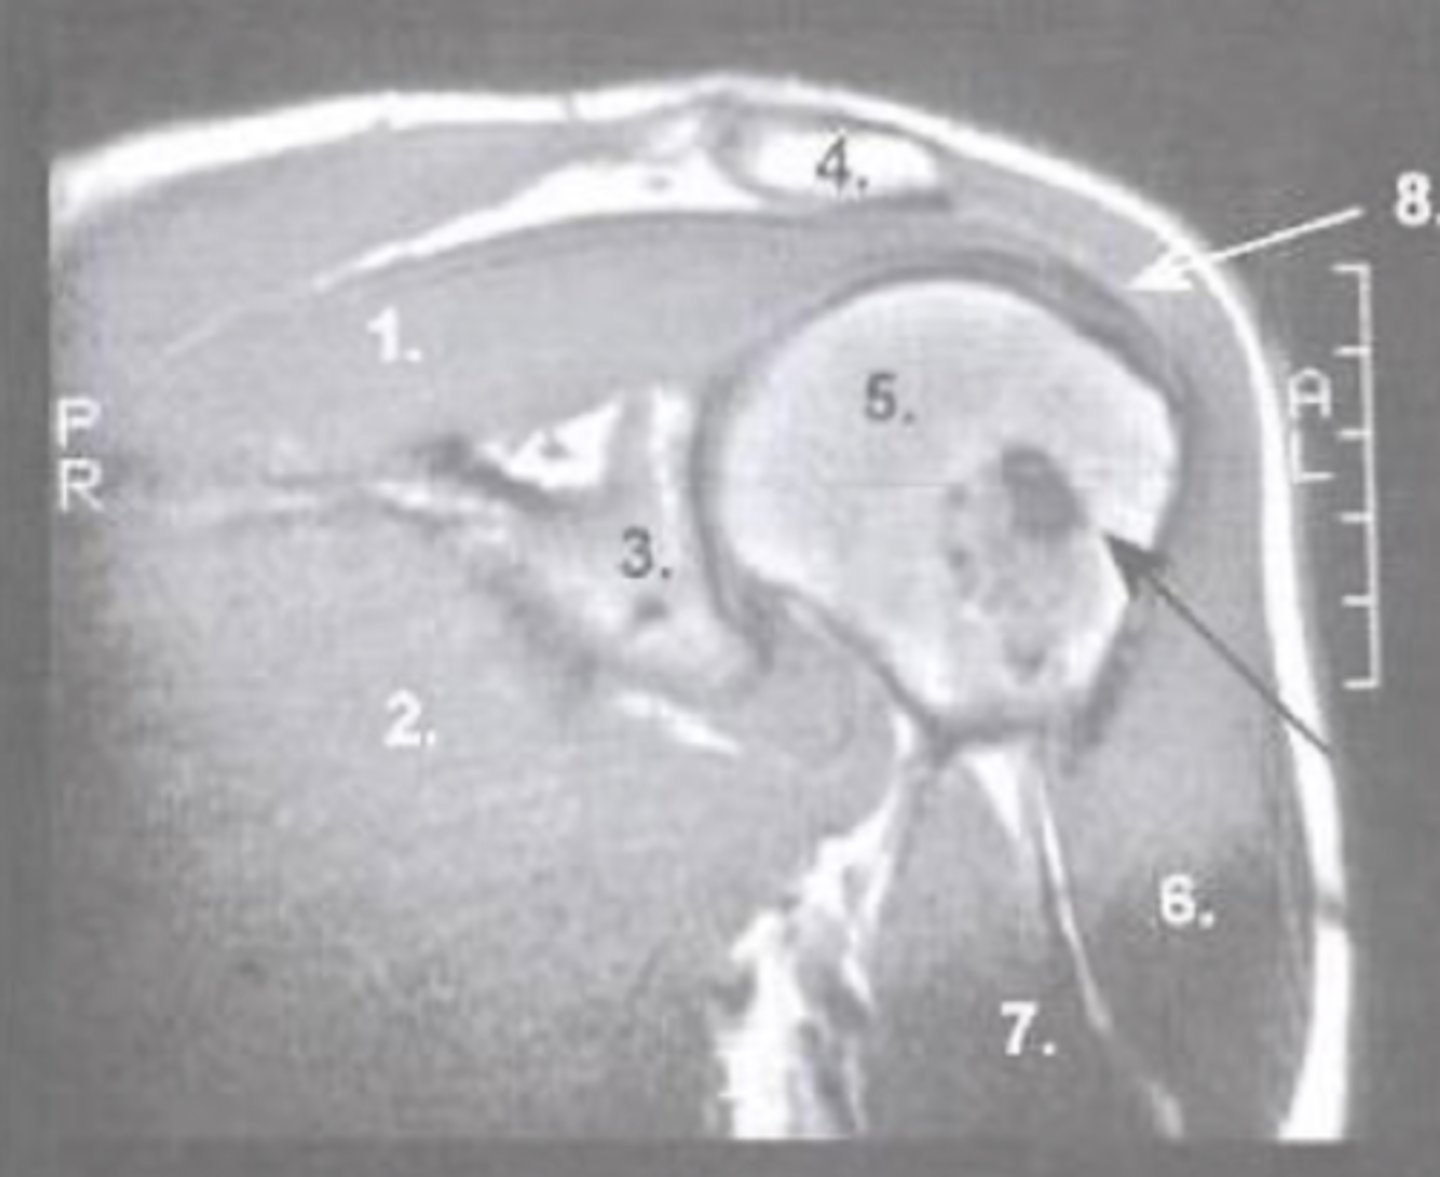

Supraspinatus muscle

What is number 1?

Pec major

What is number 2?

Glenoid

What is number 3?

Acromion

What is number 4?

Humeral Head

What is number 5?

Deltoid

What is number 6?

Biceps Long Head

What is number 7?